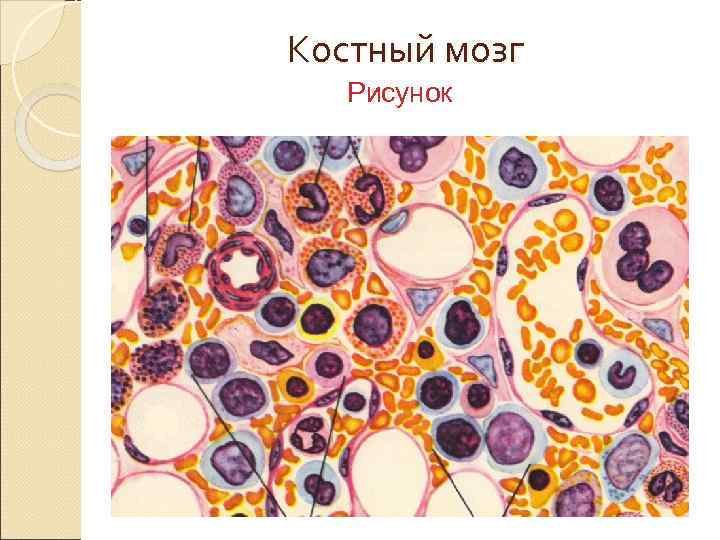

Изучение костного мозга: анатомия и функции